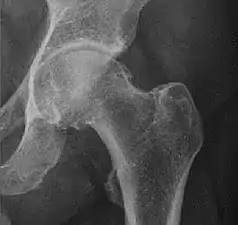

In the adult hip there are important landmarks to be recognized on plain film radiographs:[3]

- The iliopectineal or iliopubic line is formed by the arcuate line of the ilium and the superior border of the superior pubic ramus up to the pubic symphysis. It conforms to the inner margin of the pelvic ring and it is part of the anterior column of the acetabulum.

- The ilioischial line of Köhler begins at the medial border of the iliac wing and extends along the medial border of the ischium to end at the ischial tuberosity. It is part of the posterior column of the acetabulum.

- The acetabular floor.

- The teardrop represents a summation of shadows. Its medial aspect corresponds to the inner cortex of the pelvis and the lateral edge with the acetabular notch and the anteroinferior portion of the quadrilateral plate. It is not present at birth but gradually develops due to pressure of the femoral head.